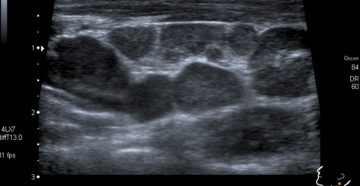

Узи лимфоузлов шеи и в подмышке: что показывает и как проводится Эндокринолог высшей категории Анна…